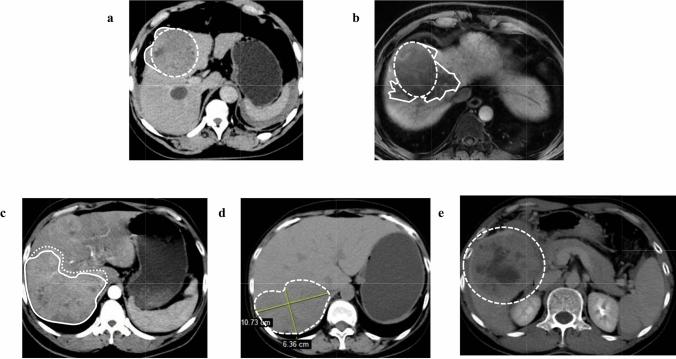

Immune checkpoint inhibitors (ICIs) are playing a significant role in the treatment of hepatocellular carcinoma (HCC). This study aims to explore the prognostic value of alpha-fetoprotein (AFP) and initial tumor shape irregularity in patients treated with ICIs.

In this retrospective, multi-center study, 296 HCC patients were randomly divided into the training set and the validation set in a 3:2 ratio. The training set was used to evaluate prognostic factors and to develop an easily applicable ATSI (AFP and Tumor Shape Irregularity) score, which was verified in the validation set.

The ATSI score was developed from two independent prognostic risk factors: baseline AFP ≥ 400 ng/ml (HR 1.73, 95% CI 1.01-2.96, P = 0.046) and initial tumor shape irregularity (HR 1.94, 95% CI 1.03-3.65, P = 0.041). The median overall survival (OS) was not reached (95% CI 28.20-NA) in patients who met no criteria (0 points), 25.8 months (95% CI 14.17-NA) in patients who met one criterion (1 point), and 17.03 months (95% CI 11.73-23.83) in patients who met two criteria (2 points) (P = 0.001). The median progression-free survival (PFS) was 10.83 months (95% CI 9.27-14.33) for 0 points, 8.03 months (95% CI 6.77-10.57) for 1 point, and 5.03 months (95% CI 3.83-9.67) for 2 points (P < 0.001). The validation set effectively verified these results (median OS, 37.43/24.27/14.03 months for 0/1/2 points, P = 0.028; median PFS, 13.93/8.30/4.90 months for 0/1/2 points, P < 0.001).